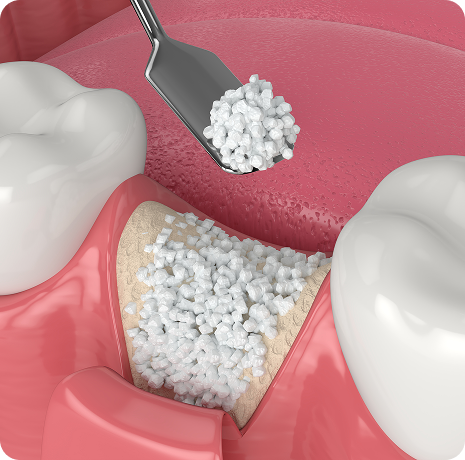

임플란트와 사랑니 발치는 외과적 시술로 잇몸을 절개하는 외과적 시술은

짧으면 짧을 수록 시술 후 붓기와 통증이 최소화됩니다.